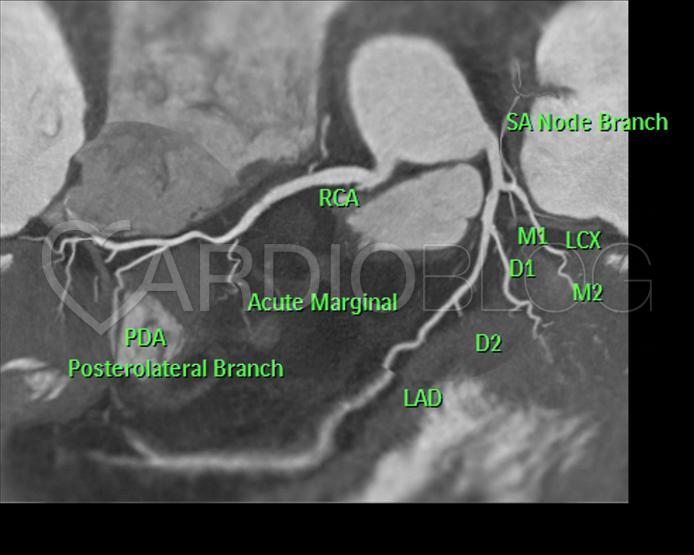

A 2D coronaria “térkép” a bal és a jobb coronariakat egy síkban mutatja. Jelentős fokú coronaria atherosclerosis, lumenszűkület biztonsággal kizárható.